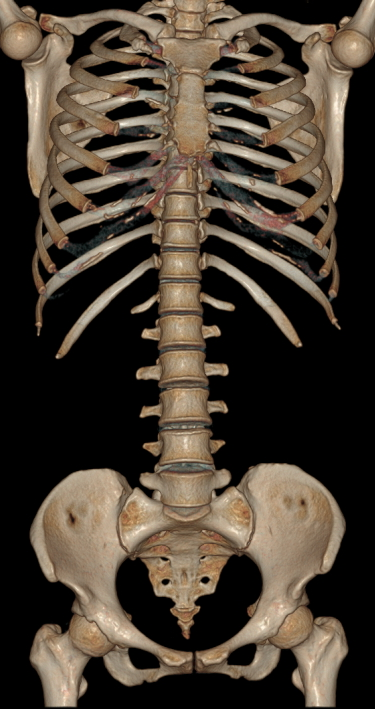

针对胸痛、脑出血、外伤、急腹症等多种急诊检查场景,天河640层CT提供全速急诊方案,检查时间最短化,图像评估直观化,为抢救生命争分夺秒。0.25秒/圈的机架转速为业内最快。

图片说明:急诊外伤胸部腹部骨盆扫描时间4.5秒完成。